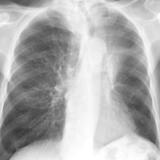

Gallery Lobar Collapse

Lobar Collapse

LUL Collapse

Album: LUL Collapse

LLL Collapse

Album: LLL Collapse

RLL Collapse

Album: RLL Collapse

RUL Collapse

Album: RUL Collapse

RML Collapse

Album: RML Collapse